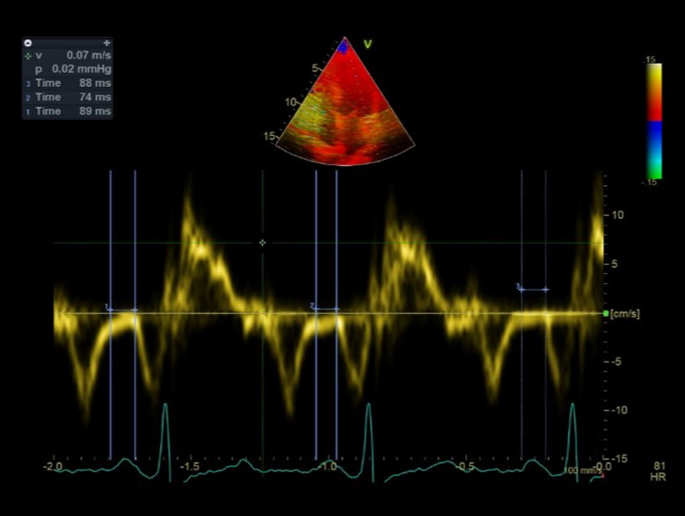

Time intervals from the beginning of P-wave to beginning of A´ wave from the lateral mitral annulus in tissue doppler imaging was recorded as the intra-atrial electromechanical delay (Fig. 1). Average values of these indexes obtained from 3 consecutive cardiac cycles were used for analysis14,15.